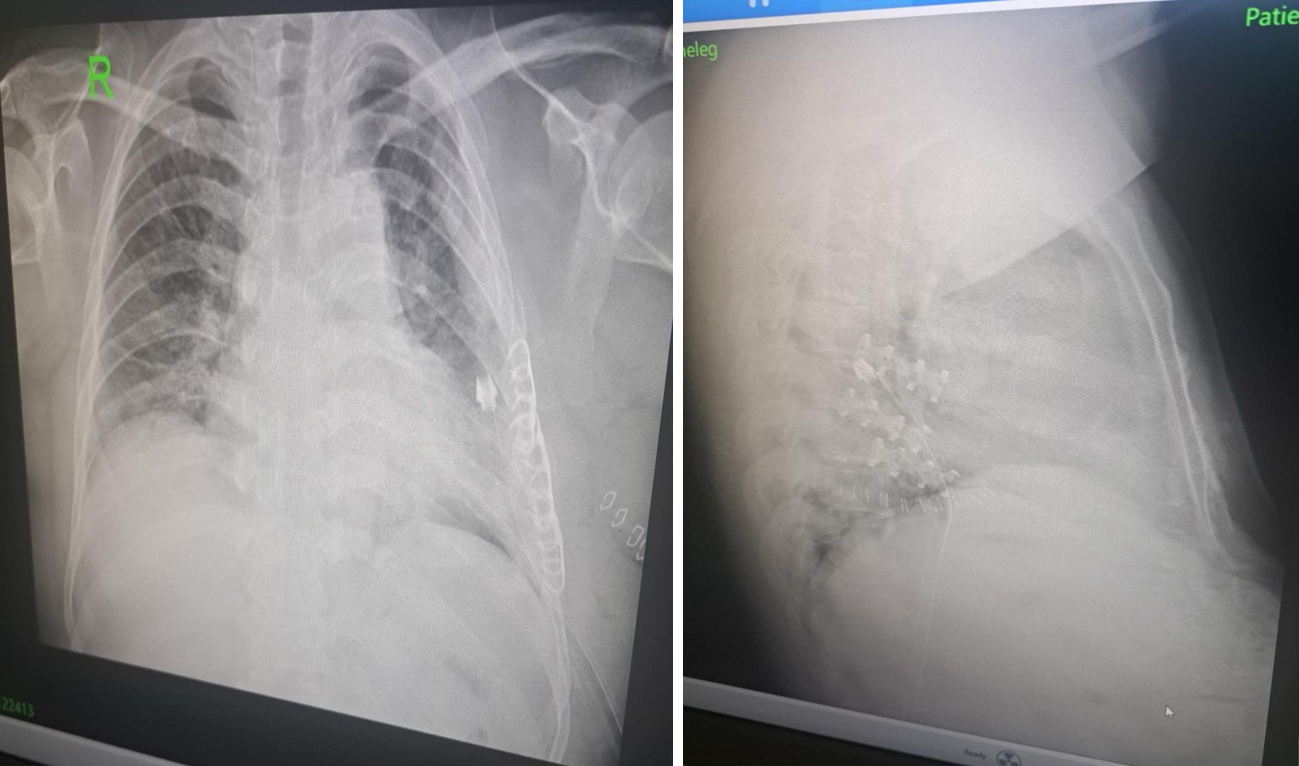

ГССҮТ-ийн Хавсарсан гэмтлийн мэс заслын тасгийн эрхлэгч П.Баярсайхан, Мэс засал, мэдээгүйжүүлэгийн нэгдсэн тасгийн сувилагч Б.Алтанцоож, жолооч М.Пүрэвбаатар нарын алсын дуудлагын баг энэ сарын 26-нд Говьсүмбэр аймагт ажиллажээ. Энэ үеэр авто ослын улмаас цээжний хөндийн хавсарсан хүнд гэмтэл болон олон хавирганы тогтворгүй хугаралтай, амьсгалын дутагдалд орсон өвчтөнд мэс заслын яаралтай тусламж үзүүллээ.

Тодруулбал, тус алсын дуудлагын баг бүрэлдэхүүн Говьсүмбэр аймгийн нэгдсэн эмнэлгийн мэс заслын эмч Д.Наранбаатар, мэдээгүйжүүлэгийн эмч Э.Алтанхуяг, мэдээгүйжүүлэгийн сувилагч Н.Наранбаатар, мэс заслын сувилагч Д.Дэлгэрмаа, асрагч н.Отгонсүрэн нартай хамтран мэс засал хийсэн байна. Өдгөө өвчтөний биеийн байдал тогтворжиж, Эрчимт эмчилгээний тасгаас шилжин, эмийн эмчилгээ хийлгэж буй.